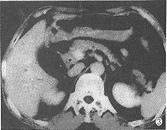

CT表现:(1)胰头轻度增大2例,约3.5cm×3.0cm,胰体、尾部相对缩小;胰钩突饱满、圆隆、分叶9例。 (2)胰头局限性低密度区5例(图1),大小约1.5cm×1.5cm~3.0cm×3.0cm,2例位于胰头前部,向外突起,边界较清楚,3例位于胰头内,边界不清,与胰腺组织呈移行状。2例胰头增大伴有弥漫性密度轻度减低,9例胰钩突密度减低,其中1例密度显著减低,但形态正常。十二指肠降部内侧壁局限性结节3例(图2),大小约1.5cm×2.0cm~2.0cm×2.0cm,密度与软组织相同,边缘清楚。增强扫描胰头病灶呈低密度或不均匀低密度区,十二指肠内侧壁结节有明显强化。 (3)胆总管下端软组织结节、局部管壁增厚、下段管壁均匀增厚各1例(图3),肝内胆管扩张18例,胆总管扩张19例,胆总管下端突然中断16例,逐渐变窄3例,胰管扩张19例。

图1 胰头腺癌。胰头内局限性低密度区,形态不规则,边缘不清楚,伴有胰、胆管扩张 图2 Vater's壶腹绒毛腺瘤恶变。CT表现为胆总管下端结节,突入十二指肠内侧壁 图3 胆总管癌。胆总管壁均匀增厚,有强化,与周围胰头分界不清,与炎症表现相似,手术见肿瘤沿胆总管壁浸润,达肝门,并有肝门淋巴结转移 图4 胰头炎症。胰头弥漫性肿大,内见散在小点状低密度区,其间胰头实质密度均匀,胰头与十二指肠紧密粘连 图5胆总管下端炎症。CT表现为胆总管下端一侧壁局限性增厚,以上胆道有少许积气,病理切片可见纤维组织增生及慢性炎细胞浸润 图6 胰头癌合并炎症。胰头后部(腔静脉左前侧)见边缘模糊小低密度区,于胰颈部有一炎性假囊肿